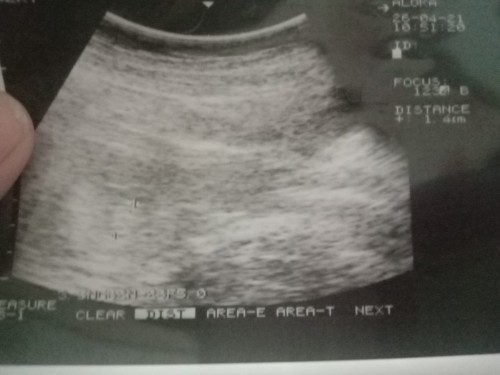

เราได้8วีคแร้ว ไปอัลเตอซาวมาจ้า เหงหัวใจน้องเหง น้องแร้วจ้า

วันนี้หมอนัดไปซาวิกครั้งจ้า พบน้อง หัวใจเต้นปกติจ้า ขอบคุนกำลังใจแม่ๆนะค่ะ

ตอน8weekค่ะ ปัจจุบัน25+1ค่ะ

ตอน 8w ปัจจุบัน 30wค่ะ